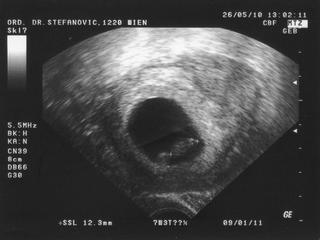

teraz sme este vacsi to je fotka z 26.5.